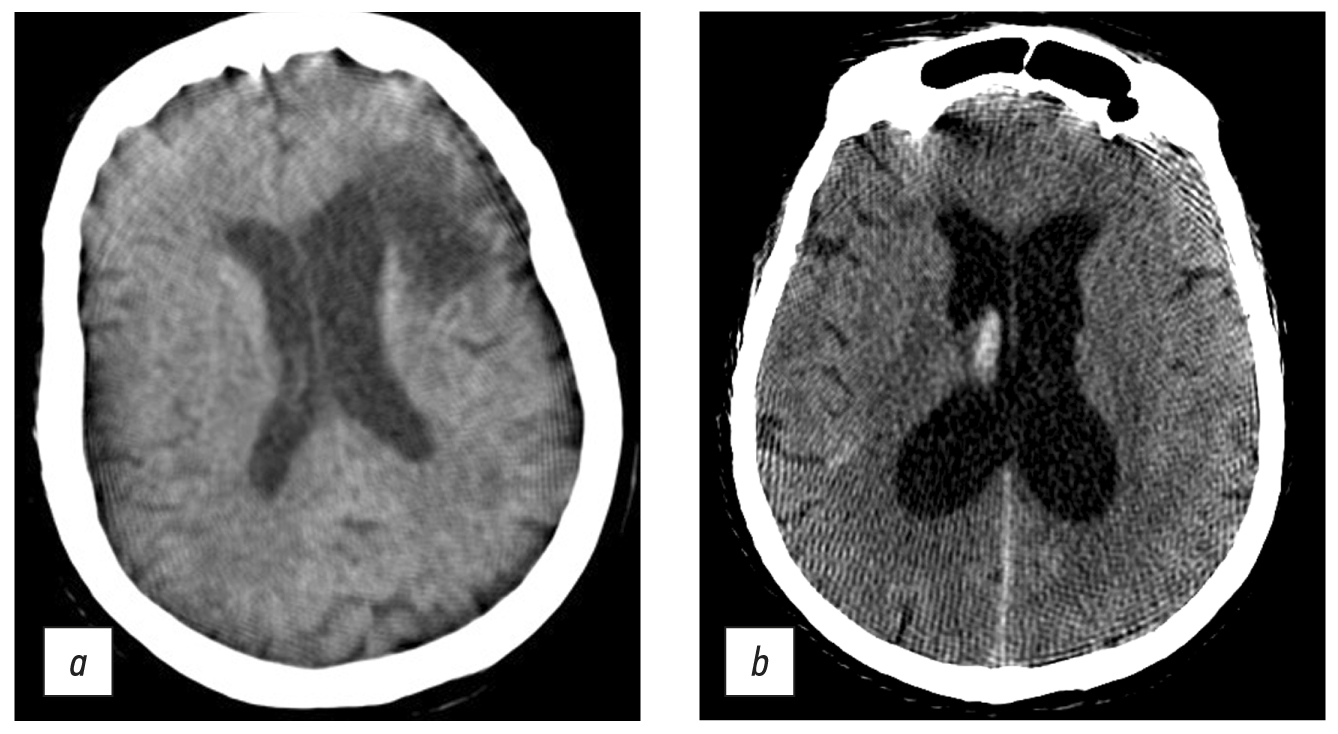

Chest CT was conducted in the majority of cases to obtain a diagnosis or to provide continuing observation for patients with COVID-19 pneumonia. The scanning parameters (Table 1) enable us to obtain images of adequate quality to differentiate between viral pneumonia, cardiogenic pulmonary edema, and bacterial pneumonia. Fig. 5 shows CT data for COVID-19-associated viral pneumonia patients.

Fig. 5. Axial computed tomographic slices of chest organs in the lung window: (a) polymorphic, predominantly subpleural areas of ground-glass opacity, corresponding to the CT image of viral pneumonia (including COVID-19), CT-1, and (b) multiple polymorphic areas of parenchyma compaction with a tendency to merge, with ground-glass opacity areas and mild reticular changes, CT-3.

A mobile CT generated acceptable quality chest CT images detecting viral pneumonia (see Fig. 5 a), and the patient capacity was sufficient for a temporary hospital with 1,300 beds in overload circumstances. The peak load was 110 scans per day, with an average of 44. This system differs from modular and mobile CTs mounted on trailers [7], mostly due to the use different types of CT.